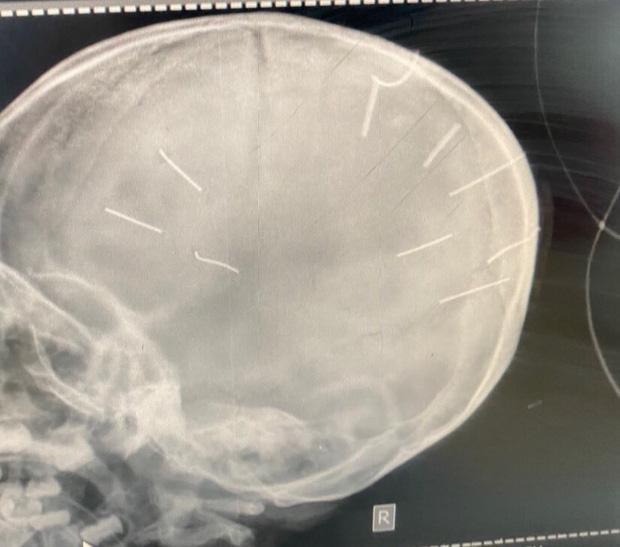

Hình ảnh chụp X-Quang hộp sọ bé gái với 9 hình thể nghi là đinh (Ảnh: Bệnh viện Đa khoa huyện Thạch Thất cung cấp)

Theo ông Kiên, Bệnh viện Đa khoa Xanh Pôn đã tiến hành chụp cắt lớp dựng hình, nhận thấy có những hình ảnh giống những đinh gỗ ở sọ và tổ chức não, tổng cộng 9 cái. Hiện, bé gái tiên lượng rất nặng.